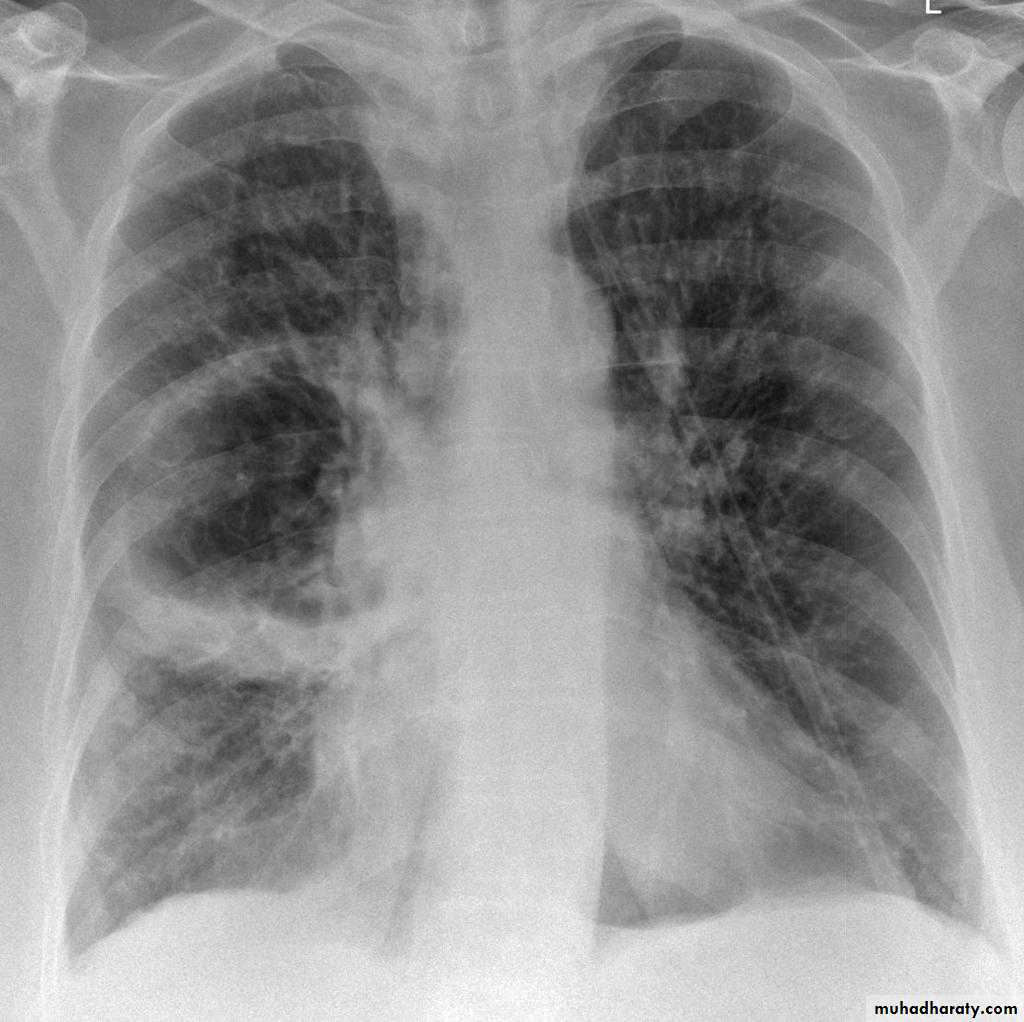

Pulmonary metastases are common and the result of metastatic spread to the lungs from a variety of tumors and can spread via blood or lymphatics.1.Cannonball metastases refer to large well circumscribed, round multiple opacities like cannonballs

2.lymphangitis carcinomatosis , is the term given to tumor spread through the lymphatics of the lung , and is most commonly seen secondary to adenocarcinoma Unfortunately up to a quarter of patients with subsequently established lymphangitic carcinomatosis have normal chest x-rays . When abnormal the most common finding is of a reticulonodular pattern, with thickening of the interlobular septae which may resemble Kerley B lines + /- pleural effusion .

3.innumerable small metastases (miliary pattern).